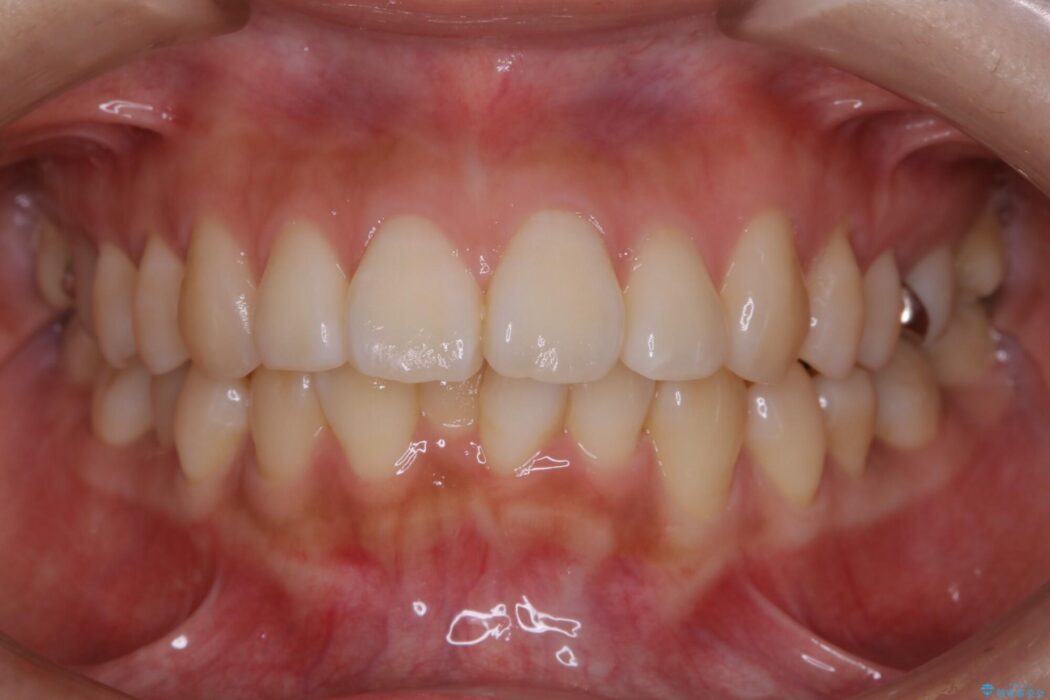

治療後について

患者様の意識も高く、しっかりとマウスピースを装着していただけたこともあり満足できる仕上がりとなりました。

本症例では最大量の移動もあり治療期間が掛かってしまいましたが、非抜歯でマウスピース矯正をしたいというご希望に応えることができました。